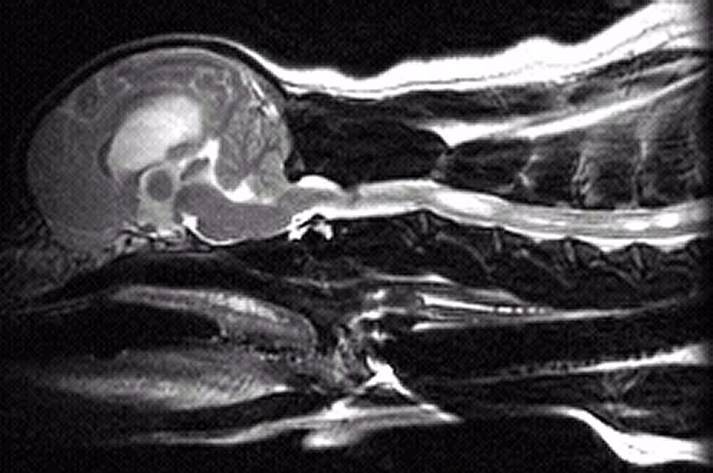

2 years old

Had SM symptoms and has since had surgery

Moderate malformation/squashing of

cerebellum

Herniation of cerebellum

Medulla kinked/squashed

Large syrinx starting just beyond C1